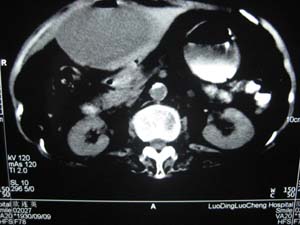

标题: CT15625:女性78Y,十天前胃镜示胃穿孔,现低热 [打印本页]

标题: CT15625:女性78Y,十天前胃镜示胃穿孔,现低热

肝脓肿/膈下脓肿?

膈下脓肿

隔下肿脓.

支持--膈下脓肿

膈下及肝脓肿。

考虑多发性肝脓肿。